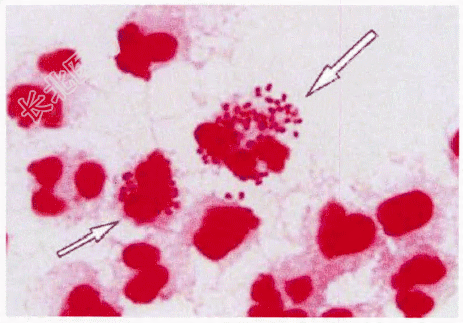

- 简答题3、该患者阴道分泌物涂片后行革兰染色结果如图所示,图中可见的有形成分有?